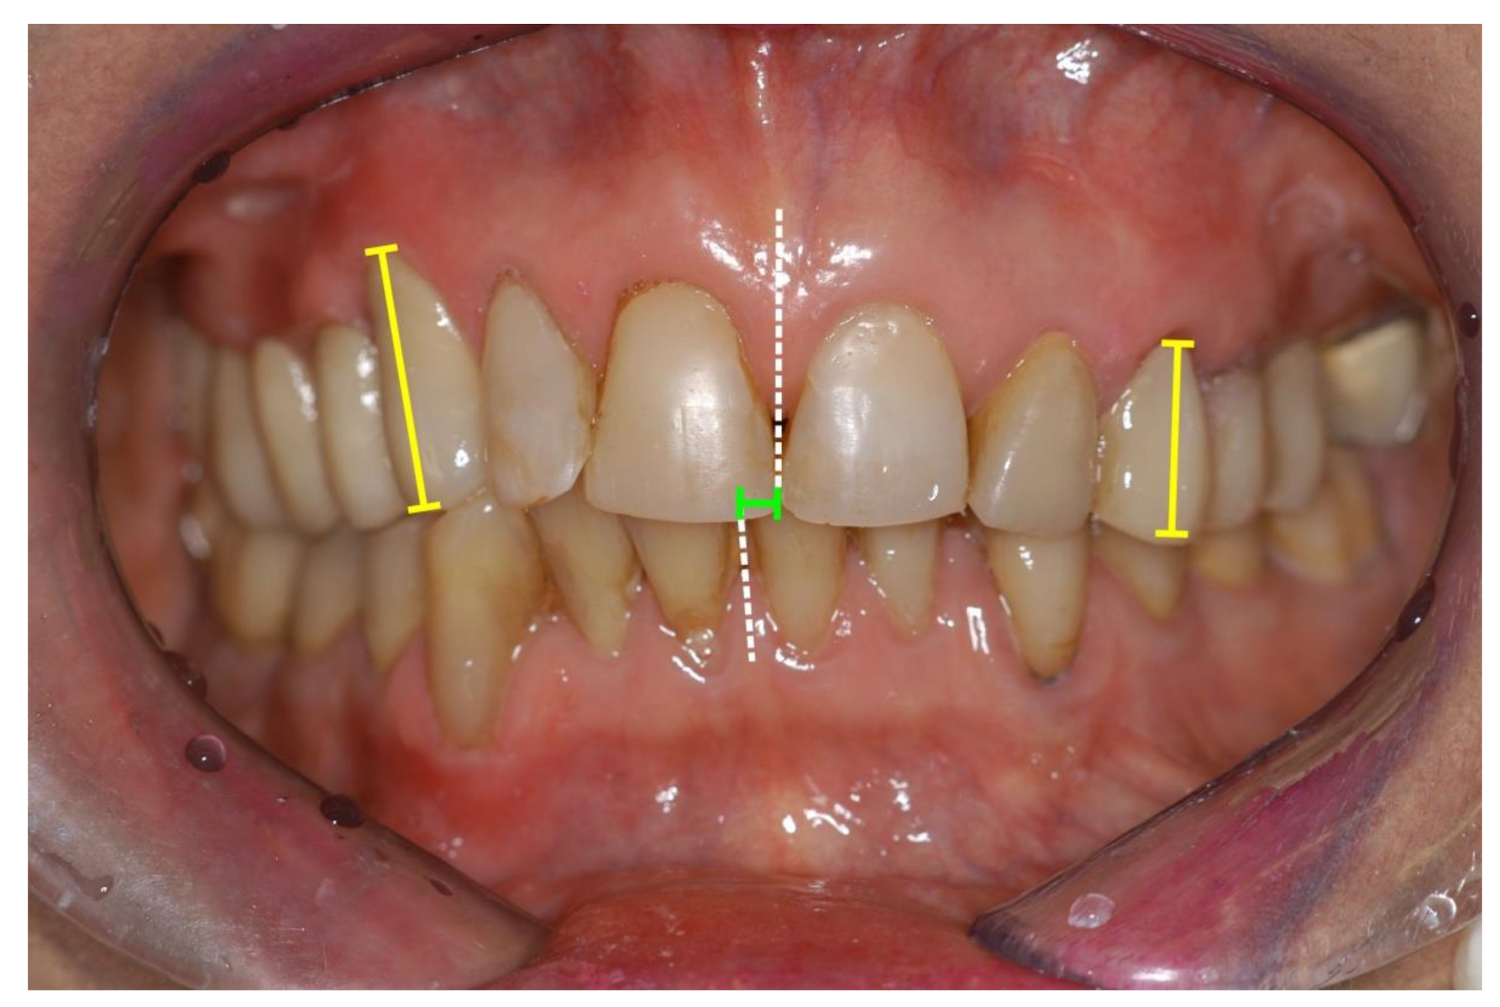

Teeth and gingival tissues are visible during an expressive smile. The observer’s attraction to the perioral region and the emotional signal of the smile has an important impact on attractiveness rating. Asymmetrical crown length and gingival height discrepancies and midline shifts were frequently examined. Most authors came to the conclusion that professionals, especially orthodontists, were more sensitive to asymmetrical changes than laypersons as far as crown length was concerned [23,71,72,73,74,75,76], though difference between laypersons and professionals was not significant in every study group. Anterior midline shifts of the upper central incisor midline in relation to the facial midline had a negative impact on the rated attractiveness at a discrepancy of 1 mm or more to the right and 2 mm or more to the left side, respectively [77]. Figure 6 shows a case with canine coronal height asymmetry and maxillary to mandibular midline shift.

Figure 6.

Anterior teeth of a 64-year-old female patient, exhibiting mandibular midline shift (green line), lower incisor angulation (white dotted lines) and crown height discrepancy between right and left incisors and canines (yellow lines). Treatment included surgical crown lengthening and crowns and fixed partial dentures from left canine to the left molar region. The patient’s main concern was to improve her aesthetic appearance.